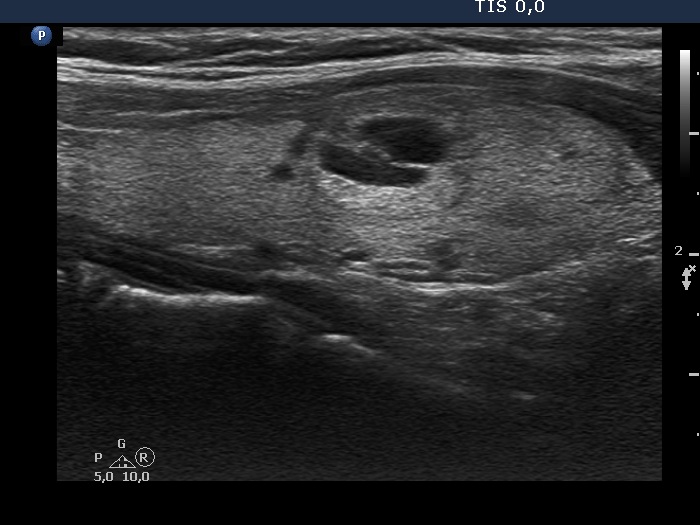

100 consecutive cases of papillary cancer - case 071

Clinical presentation: A 40-year-old woman requested a follow-up. I met her first 11 years ago when a multinodular goiter was found. There was a suspicious nodule in the isthmus with the dimensions of 11x9x14 mm. At that time the patient refused cytology.

Ultrasonography. The thyroid was echonormal. There were two echonormal/hyperechoic nodules in the right lobe. The nodule in the isthmus was hypoechoic, had numerous microcalcifications and showed blurred borders. The dimensions of the lesion were 11x10 13 mm, width x depth x length, respectively.

Cytology resulted in papillary cancer.

Histopathology revealed a T1N0 papillary cancer. The dimensions measured during pathological examination were 10x8x12 mm.